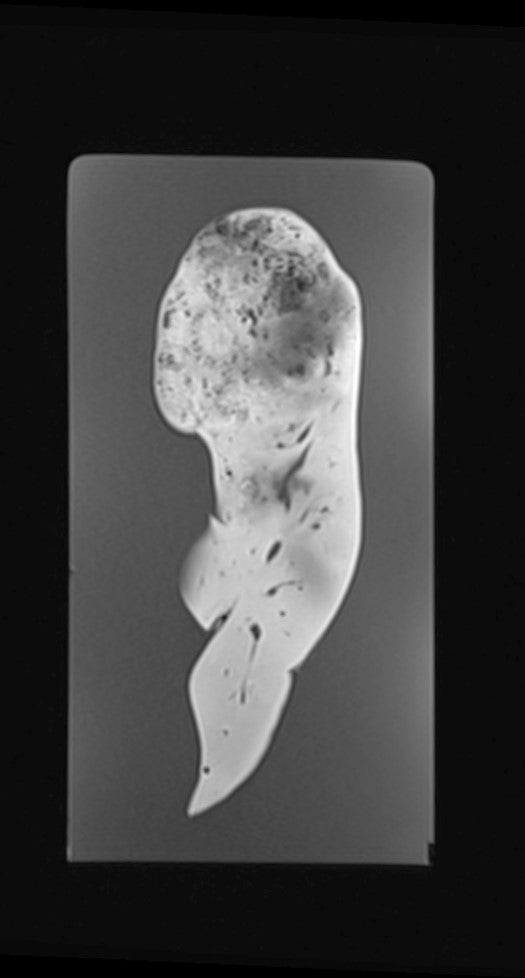

Kidney - Nephroblastoma